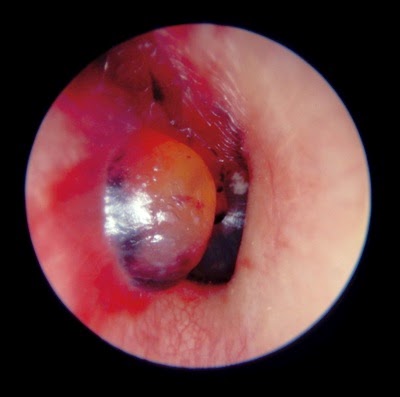

External Otitis An Overview Sciencedirect Topics

Otitis externa malignant treatment icd 9 what is symptoms acute chronic causes. It is inflammatory infectious condition occur in external auditory. 001 cholera 0010 cholera due to vibrio cholerae 0011 cholera due to vibrio cholerae el tor 0019 cholera unspecified 002 typhoid and paratyphoid fevers. Free official information about 2012 and also 2013 2015 icd 9 cm diagnosis code 1369 including coding notes detailed descriptions index cross references and.